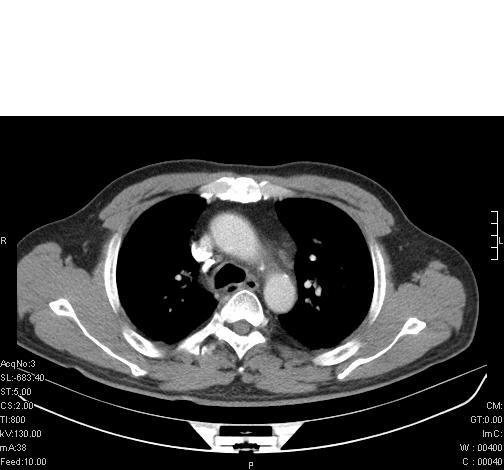

标题: CT6685:右肺阻塞性炎症,增强CT。

前几天,发了患者的平扫片,患者抗炎一周后增强扫描。右中叶病灶吸收明显,但下叶病灶未见明显吸收。右肺门可见结节影,看来凶多吉少

右肺下叶支气管管腔狭窄,管壁增厚,右下肺见斑片状高密度影,考虑右侧肺门中心肺癌伴阻塞性肺炎

右肺下叶支气管壁明显增厚,考虑癌症并阻塞性炎症、肺门淋巴结肿大

考虑右肺癌并阻塞性炎症、肺门淋巴结肿大

右肺下叶支气管壁不规则增厚,右肺下叶有斑片状影分布。考虑右肺中央型肺癌伴右肺下叶阻塞性改变。建议支纤镜检查。平扫比增强较好显示了病变情况。

右主支气管狭窄,管壁增厚。考虑右中心性肺ca伴阻塞性肺炎。

既然抗炎治疗有效,可继续治疗;右肺下叶支气管管腔狭窄,管壁增厚,右下肺见斑片状高密度影,右侧主支气管后见结节影(淋巴结?),肺癌不能排出。